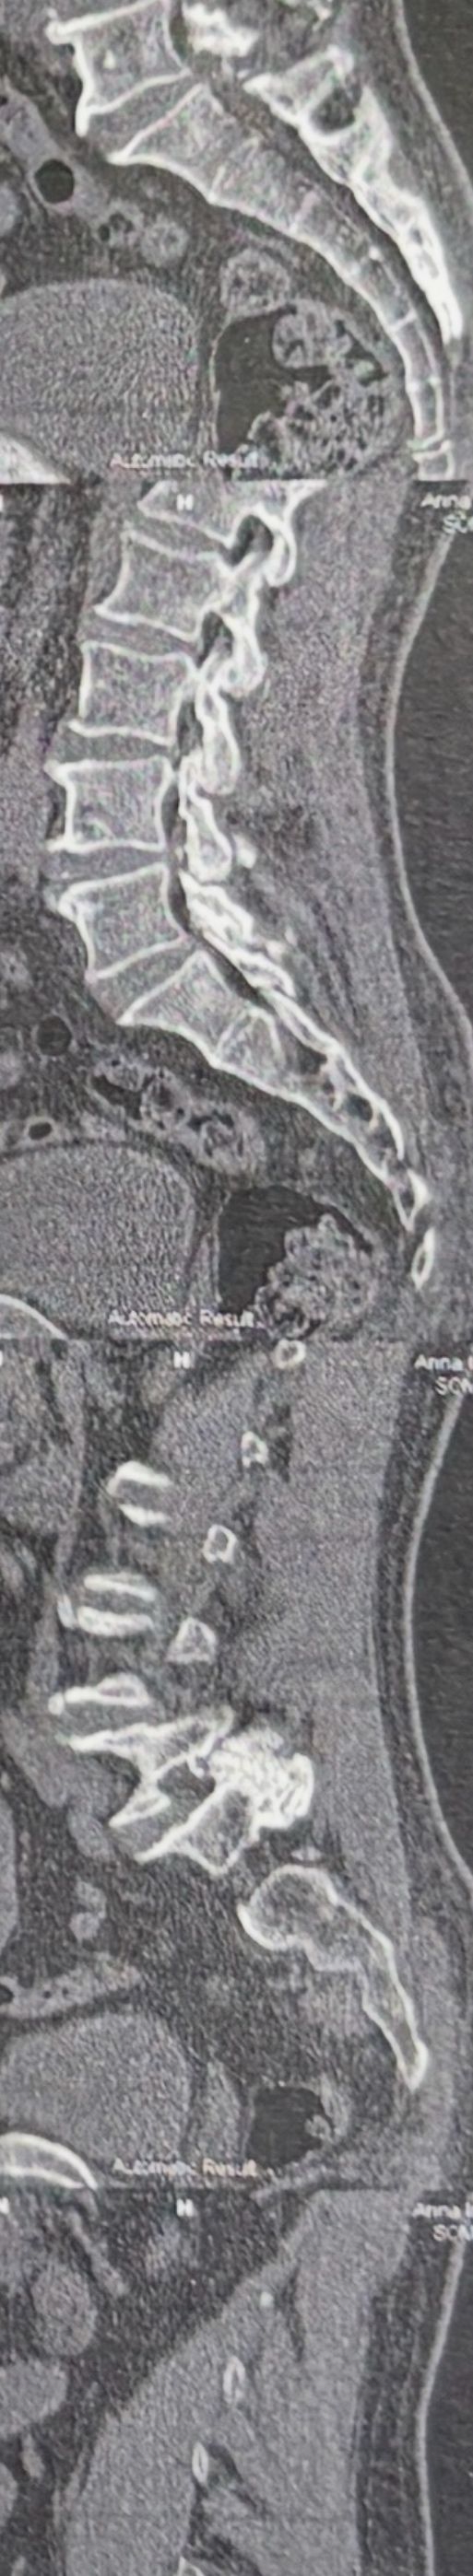

Case 10

62 years old male presented to our clinic due to legs heaveness/tireddness in walking 2 weeks ago. 9 months ago had cervical disc herniation surgery. Had no LBP, no radicular pain. All neuro exam were normal. In his mri and dynamic scan there was a big osseous mass behind L5and S1. In his x. Ray report just was mantioned DJD

Radiologist missed that large osseous mass. Radiologist missed that bony post mass in x ray and mri. We ordered CT scan.